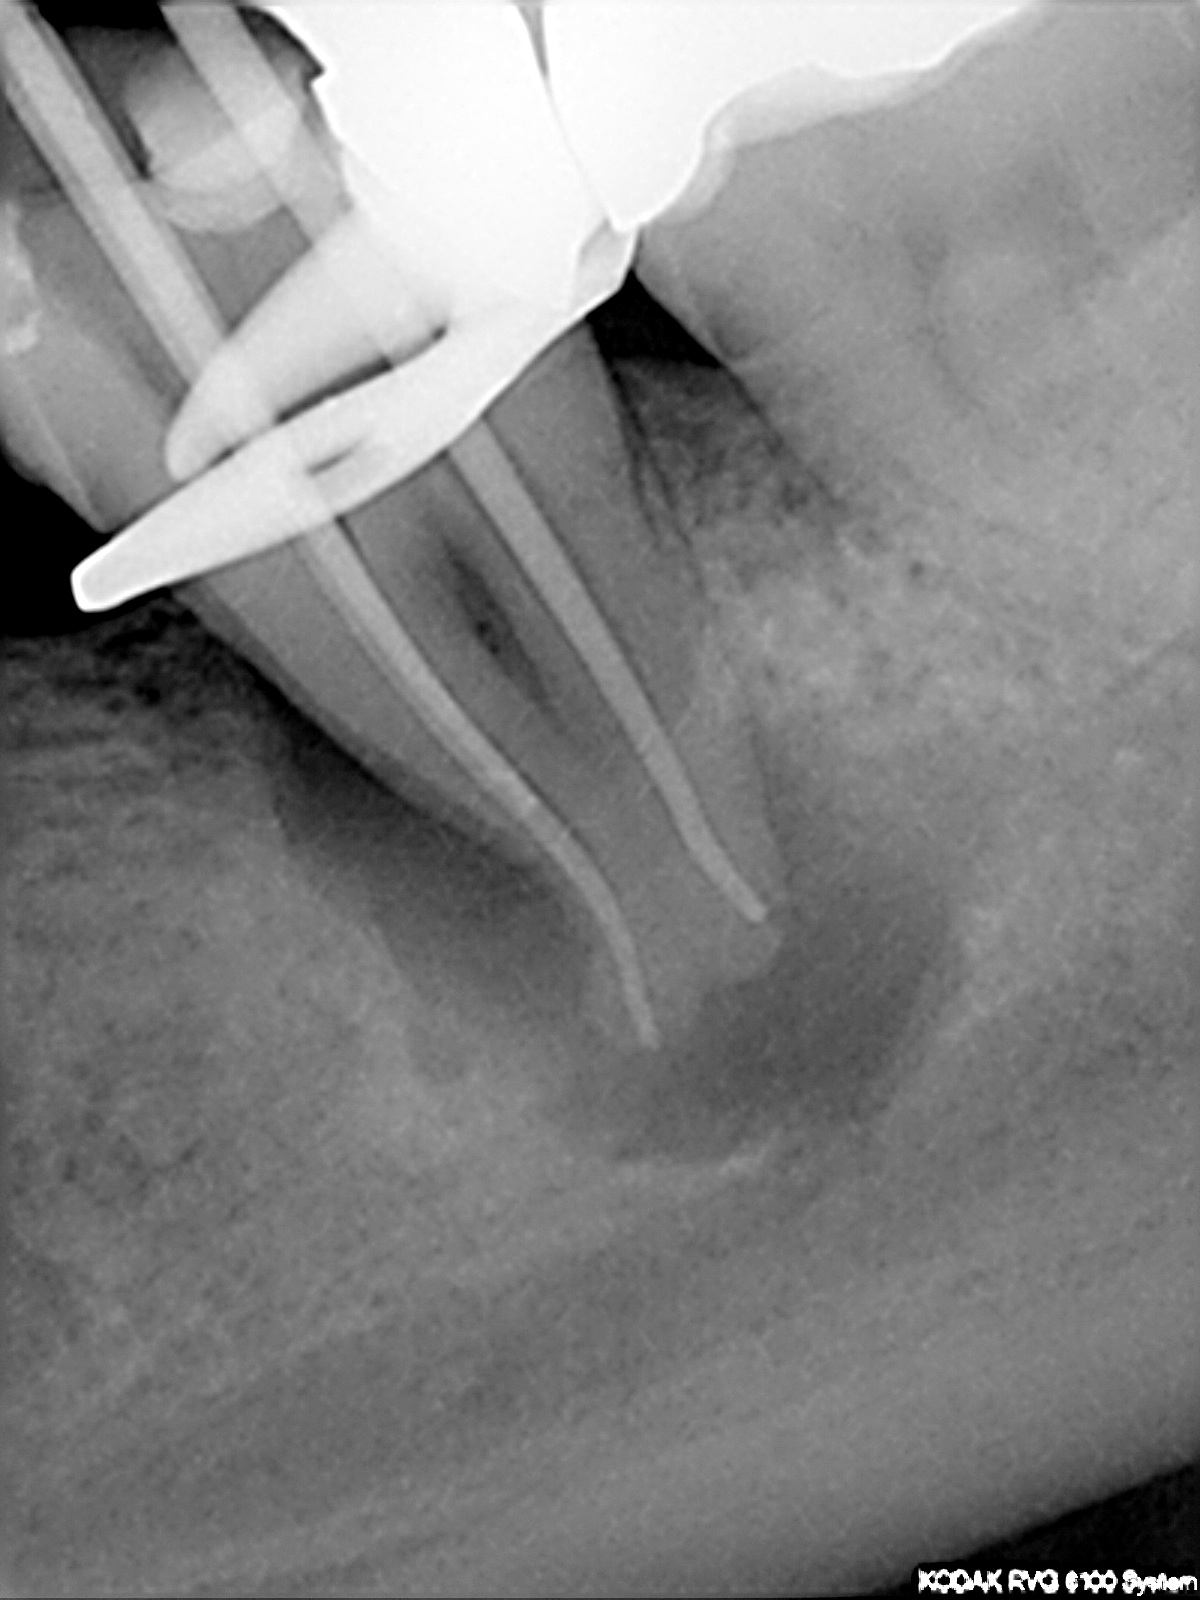

Masterpoint

1200 × 1600

Interessante Kanalanatomie (2)